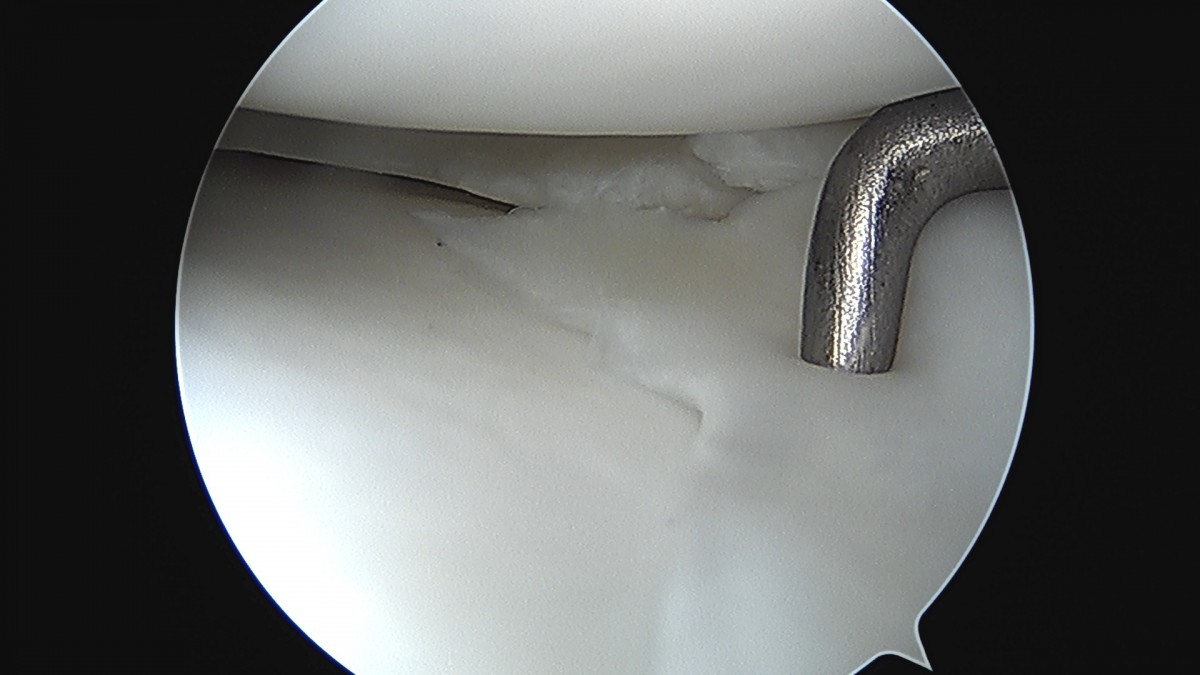

이재상원장님 무릎 반월상 연골판 절제술 김건O 환자

dae765e4d9ac96aee867c9d6292d8784_1758006493_453.jpg